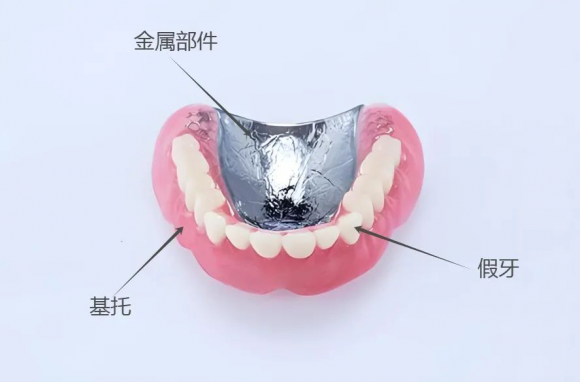

02.传统活动义齿传统活动义齿则依赖卡环固位,对邻牙存在一定侧向力,长期使用可能导致基牙松动。

・传统活动义齿:通常需要额外的固定装置,如金属卡环,但在这些动作时容易松动。

03.制作材料和美观性

・吸附性义齿:通常使用高分子材料如热塑性树脂,耐用而且美观。

・传统活动义齿:可能包含塑料基托和人工牙,虽然舒适但外观可能不如吸附性义齿。